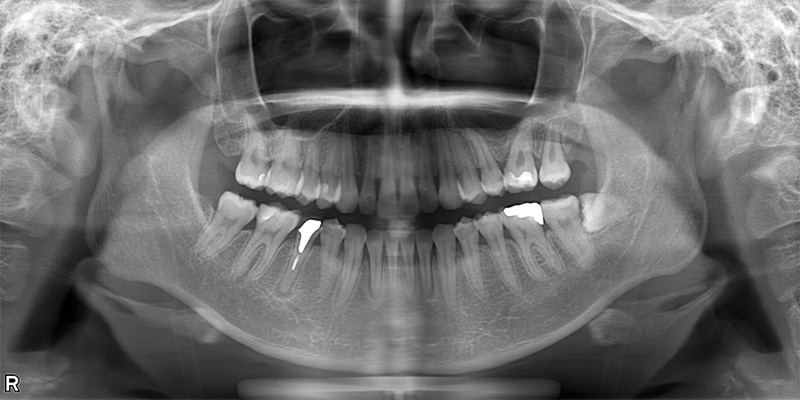

57歳男性

治療前

治療後

| 施術名 | インプラント治療 |

| 施術の説明 | インプラント治療とは、歯を抜いた所にチタン製の人工歯根を埋入し、新しく歯を入れる方法です。 |

| 施術の副作用 (リスク) | 腫れや疼痛を感じる、違和感を感じるなどの症状を生じることがあります。 |

| 施術の価格 | 53万円~+消費税 |